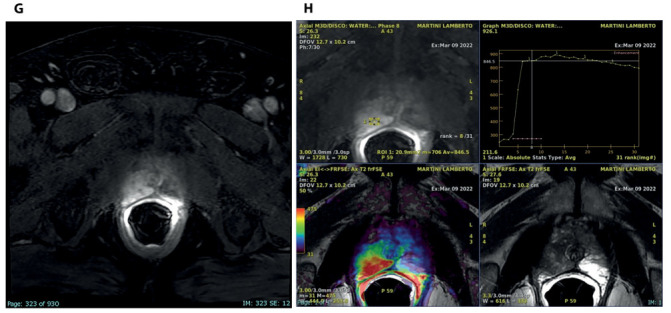

我们报告了一例63岁的男性患者,他来到泌尿外科诊所,前列腺特异性抗原值增加,直肠指检时不对称增大。该男子接受了前列腺MRI检查,随后对前列腺癌症进行了令人信服的放射学诊断。患者被指定为T3a N0疾病的临时阶段。为了证实这一诊断,进行了前列腺活检,但组织学分析报告了非特异性肉芽肿性前列腺炎(GP)。TRUS和MRI在临床和放射学上通常模拟前列腺癌症(PCa),这是一种罕见的情况,由于其非特异性症状和特定的放射学发现,这是诊断挑战。在本病例报告中,我们讨论了这种罕见临床疾病的磁共振成像特征,以帮助放射科医生及时诊断,获得正确的诊断框架。

We report the case of a 63-year-old male who came to the urology clinic with an increasing value of the prostate specific antigen and an asymmetrical enlargement at the digital rectal examination. The man was subjected to an MRI of the prostate following which a convincing radiological diagnosis of prostate cancer was made. The patient was assigned a provisional stage of disease T3a N0. In order to confirm this diagnosis, a prostate biopsy was performed but the histological analysis reported non-specific granulomatous prostatitis (GP). It is an uncommon condition that both clinically and radiologically on TRUS and MRI usually mimics prostate cancer (PCa), representing a diagnostic challenge due to its non-specific symptoms and aspecific radiological findings. In this case report we discuss the magnetic resonance imaging features of this rare clinical condition in order to help radiologists in the timely diagnosis for a correct diagnostic framing.